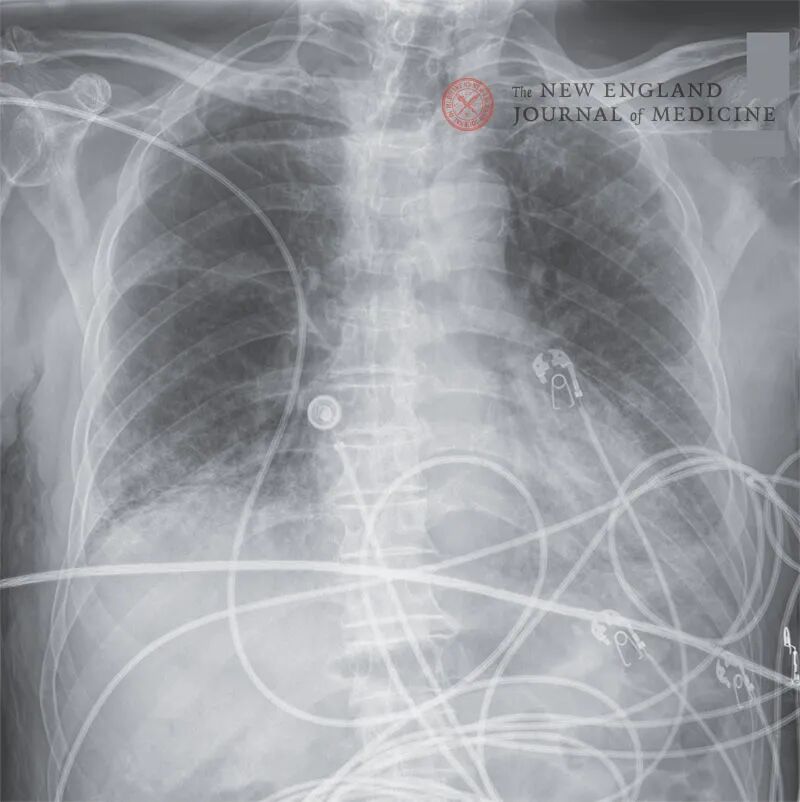

床旁胸片提示双肺呈斑片状模糊影,左肺病变范围较右肺更广泛,病变主要集中在下肺野外周带,肺门区域相对正常(图1)。此外肺尖和双肺底可见支气管扩张和网状实变影。骨盆X线检查未见骨折。

图1. 胸部X线片